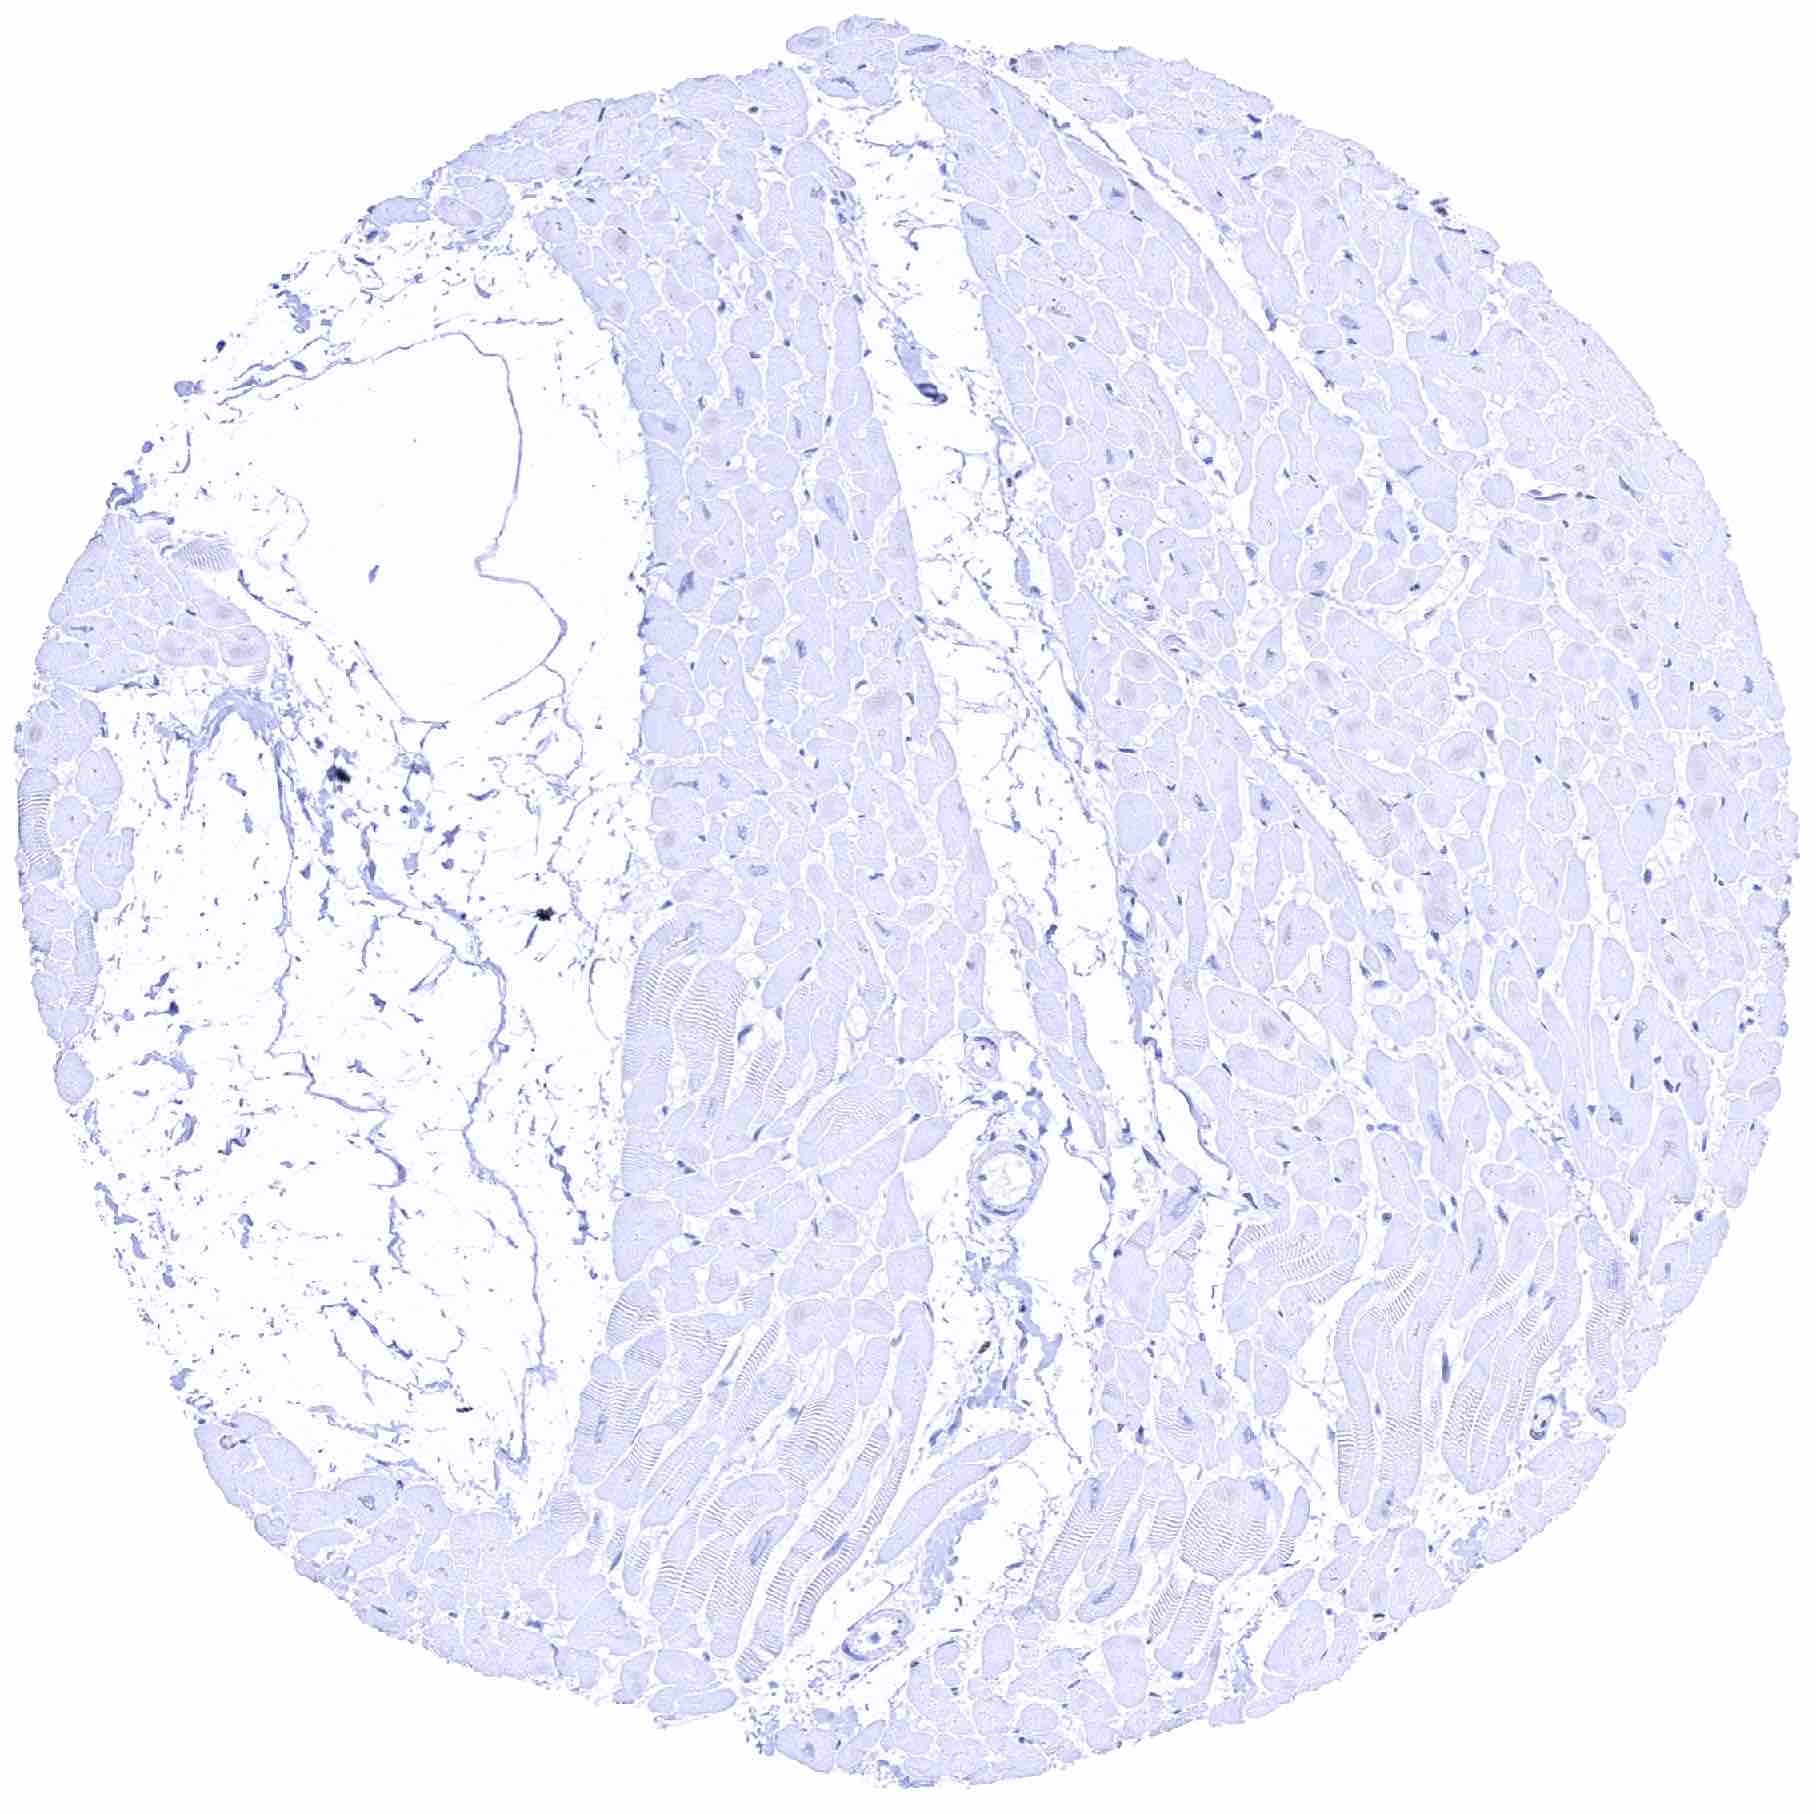

Skeletal muscle